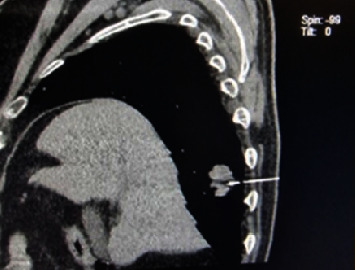

Purpose: We report our experience of diagnosing and managing metastatic adenocarcinoma of the lungs with primary manifestation to the iris and the ciliary body with the purpose to raise clinical suspicion for systemic malignancy in the presence of undetected ocular mass along with other ocular manifestations. Observations: An 82-year-old male presented with a deterioration of vision and intense pain in the right eye since the day before. With his right eye, he suddenly discerned hand movements only. Intraocular pressure in the right eye was increased. Slit-lamp biomicroscopy revealed a ciliary injection and hemorrhagic mass overlying the temporal half of the iris. The L-9 ultrasound biomicroscopy (UBM) scan documented the tumor completely infiltrating the iris and the ciliary body. We suspected a metastatic eye lesion. CT chest imaging showed a solid expansive formation of the right lung. At the Oncology Department, a fine needle aspiration biopsy was performed under the control of MSCT, which confirmed lung adenocarcinoma. Conclusions and Importance: Although very rarely, pathological changes in the uvea may indicate a metastatic occurrence that needs to be considered in the differential diagnosis. It is important to undergo a wide ophthalmological examination, which in this case included a standardized A-scan echography and UBM, which confirmed the suspicion of a tumor lesion, followed by cooperation with other medical professionals in order to discover a primary diagnosis.